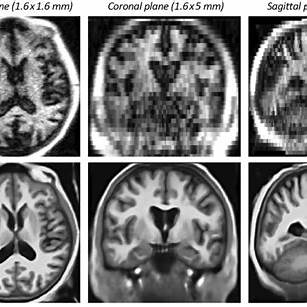

일본에서 1980년대부터 본격적으로 연구된 신린요쿠(森林浴, Forest Bathing)는 단순한 산책이 아니라 숲 환경에 의도적으로 몰입하는 심신 치유법이다. 신린요쿠 연구 중 주목할 만한 발견은 숲속 걷기가 전전두엽(prefrontal cortex) 활동을 안정화시킨다는 점이다. 전전두엽은 계획, 집중, 감정 조절을 담당하는 핵심 뇌 영역으로, 스트레스 상황에서는 과도하게 활성화되거나 반대로 기능 저하가 일어난다. 일본 지바대학교 연구팀은 숲과 도시를 비교한 fNIRS(근적외선분광법) 실험에서, 숲속 걷기 후 전전두엽의 산소화 혈류가 도시 보행보다 유의하게 낮아졌다고 보고했다. 이는 단순히 기능 저하가 아니라 과도한 긴장 해소를 의미하며, 결과적으로 뇌의 에너지 소비가 줄고 인지 효율성이 높아지는 효과로 연결된다. 즉, 신린요쿠는 전전두엽의 부담을 줄여 뇌가 과부하 없이 안정적으로 작동하도록 만드는 자연 기반 신경조절 방법이라 할 수 있다.

숲속 걷기의 또 다른 중요한 효과는 뇌파 패턴과 자율신경계의 동시 변화다. 일본 국립농업식품연구소의 실험에 따르면, 피험자가 숲속을 걸을 때 알파파는 감소하였다. 알파파 증가는 심리적 안정과 내적 평온을 반영하고, 베타파 감소는 과도한 경계와 불안을 줄여준다. 동시에 심박 변이도(HRV)가 상승하며 부교감신경계가 활성화되었는데, 이는 뇌-심장 연결 회로가 숲 환경에서 조화롭게 반응한다는 사실을 보여준다. 흥미로운 점은, 이러한 변화가 단순히 ‘걷기 운동’ 때문이 아니라 숲이라는 환경적 자극과 결합할 때 극대화된다는 점이다. 동일한 강도의 걷기를 도심에서 했을 때는 알파파·HRV 상승이 미미했으나, 숲에서는 뚜렷하게 나타났다. 이는 시각적 초록색, 나무 향 피톤치드, 새소리 등의 다감각 자극이 뇌의 전기적 리듬과 자율신경 반응을 통합적으로 안정시킨다는 의미다. 따라서 신린요쿠는 단순한 신체 활동을 넘어, 뇌파와 자율신경계를 동시에 조율하는 자연치유형 신경생리 개입이라 할 수 있다.